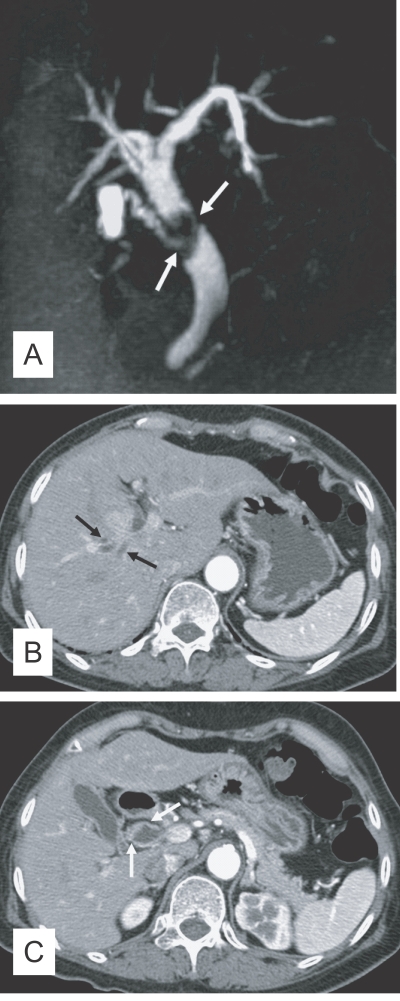

The principle imaging finding of clonorchiasis is diffuse dilatation of the peripheral intrahepatic bile ducts (Lim, 1990). However, the larger intrahepatic and extrahepatic bile ducts are not dilated or minimally dilated. The predominant dilatation of the peripheral intrahepatic ducts is due to the adult worms residing in the peripheral small bile ducts. Compared with normal subjects, many intrahepatic bile ducts are observed on cholangiography in patients with clonorchiasis due to the dilated peripheral intrahepatic bile ducts (Fig. 1A and B). Lim et al. (1992) reported "too many intrahepatic ducts" sign in 76% (22 of 29) of patients with clonorchiasis on direct cholangiography.

The presence of the fluke bodies in the peripheral bile ducts can be demonstrated on a cholangiogram (Choi et al., 1984; Lim et al., 1992). Cholangiography shows oval, elliptical, or filamentous, small filling defects within the dilated peripheral intrahepatic bile ducts, representing the flukes (Fig. 1) (Lim et al., 1992). It is a pathognomonic finding on direct cholangiography, but the defects can be obscured by the contrast medium. The filling defects by the flukes are usually small and irregular, with a uniform size on direct cholangiography, which are easily differentiated from stones (Fig. 1) (Choi et al., 1984; Lim et al., 1992; Jeong et al., 2004). Direct cholangiogram is obtained with an injection of iodine contrast material via catheter during either endoscopy or percutaneous biliary drainage (Fig. 1). Recently, non-invasive cholangiograms can be made by using MR imaging (Fig. 1) (Barish and Soto, 1997).

Fig. 1

Cholangiograms of clonorchiasis showing "too many intrahepatic ducts" signs. A. By percutaneous biliary drainage catheter (arrows) in a 58-year-old man, showing diffuse and uniform dilatation of the peripheral intrahepatic bile ducts. B. Endoscopic retrograde cholangiography in a 70-year-old man, with diffuse dilatation of the peripheral intrahepatic bile ducts, but no dilatation of the extrahepatic bile duct. C. Multiple, oval, small filling defects (arrows) within the dilated peripheral intrahepatic bile ducts, representing the flukes in a 55-year-old man. D. Magnetic resonance (MR) cholangiography in a 70-year-old man with diffuse dilatation of the peripheral intrahepatic bile ducts.

Fig. 1 Cholangiograms of clonorchiasis showing "too many intrahepatic ducts" signs. A. By percutaneous biliary drainage catheter (arrows) in a 58-year-old man, showing diffuse and uniform dilatation of the peripheral intrahepatic bile ducts. B. Endoscopic retrograde cholangiography in a 70-year-old man, with diffuse dilatation of the peripheral intrahepatic bile ducts, but no dilatation of the extrahepatic bile duct. C. Multiple, oval, small filling defects (arrows) within the dilated peripheral intrahepatic bile ducts, representing the flukes in a 55-year-old man. D. Magnetic resonance (MR) cholangiography in a 70-year-old man with diffuse dilatation of the peripheral intrahepatic bile ducts.